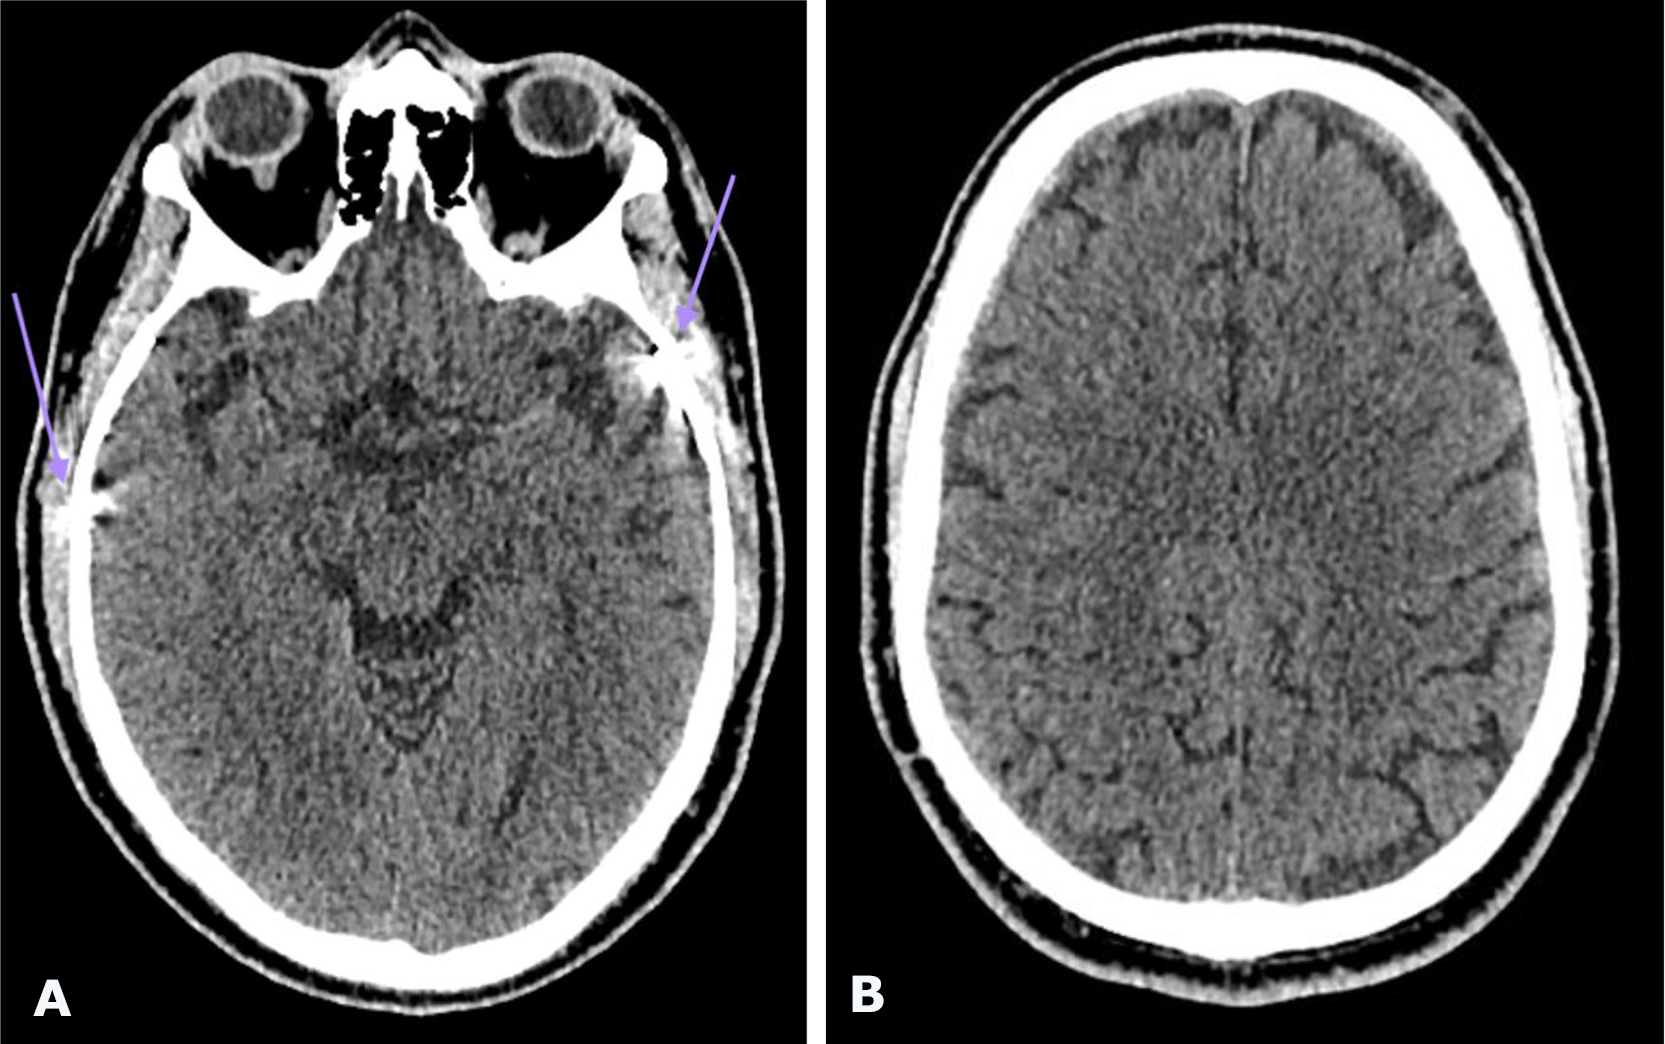

Non-contrast brain CT revealed bilateral chronic subdural hematomas (cSDH) in the frontal regions. The hematoma dimensions (thickness/length/height) were 8/48/48 mm on the left and 9/132/51 mm on the right. No displacement of the midline structures of the brain was detected (Fig. 1).

Fig. 1. Preoperative brain CT: A, B—axial projections demonstrating bilateral frontal cSDH (indicated by red arrows)

The postoperative course was uneventful. The neurological status remained unchanged, and no complications were observed. The patient was discharged from the hospital on postoperative day 2. Follow-up brain CT performed 1 month after surgery (Fig. 4) demonstrated complete resolution of bilateral frontal cSDH. At follow-up examination, regression of global cerebral symptoms was noted.

Fig. 4. Postoperative brain CT: A, B – axial projections. Purple arrows indicate the radiopaque embolic agent Onyx™ within the projections of the left and right MMAs